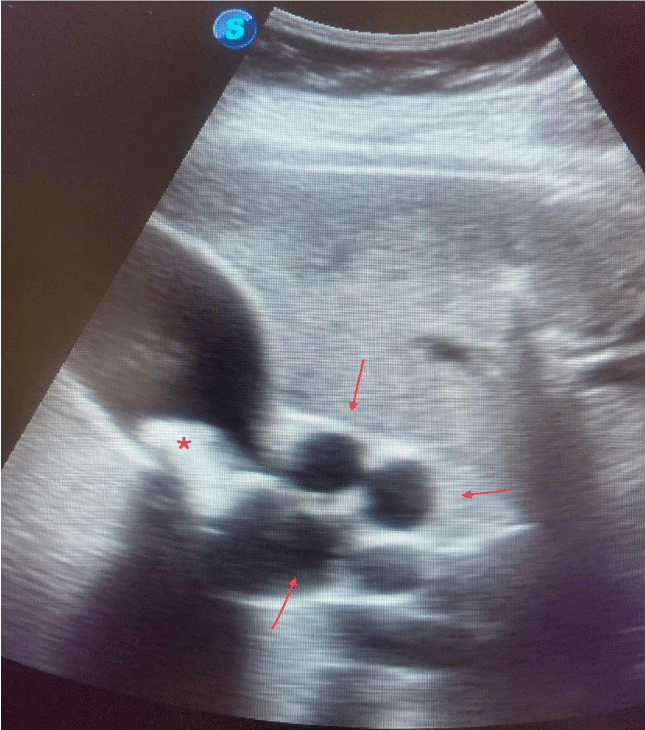

Thinking about a possible cholestatic syndrome, we performed an abdominal ultrasound in the same consultation. Where we clearly appreciate the presence of a lithiasis lodged in the infundibulum of the gallbladder along with dilation and tortuosity of the common bile duct (Figure 1).

Ultrasound signs that would indicate the possibility of MS are: contracted gallbladder with dilated intrahepatic bile duct and common hepatic duct. The caliber of the common bile duct being normal. MS is also suggested by dilation of the neck of the gallbladder, the presence of impacted cholelithiasis at the level of the neck of the gallbladder, or the abrupt change in the width of the common hepatic duct distal to cholelithiasis [9].